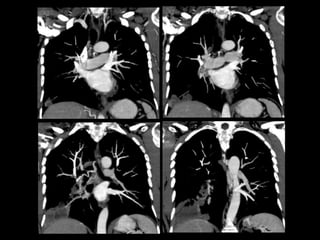

Protocolo AngioTC Torácico

• Desde base cuello hasta nivel de arterias renales

para incluir troncos supraaórticos y arterias

infradiafragmáticas.

• 0.8/1 mm. grosor de corte

• 100-120 ml contraste yodado no iónico a 4cc/sg.

• ROI en Aorta descendente.

• Reconstrucciones multiplanares y volumétricas

(MIP y VR): coronales (arterias mamarias internas

e intercostales) y axiales (arterias frénicas

inferiores y tronco celiaco).

Protocolo AngioTC Torácico •Desde base cuello hasta nivel de arterias renales para incluir troncos supraaórticos y arterias infradiafragmáticas. • 0.8/1 mm. grosor de corte • 100-120 ml contraste yodado no iónico a 4cc/sg. • ROI en Aorta descendente. • Reconstrucciones multiplanares y volumétricas (MIP y VR): coronales (arterias mamarias internas e intercostales) y axiales (arterias frénicas inferiores y tronco celiaco).